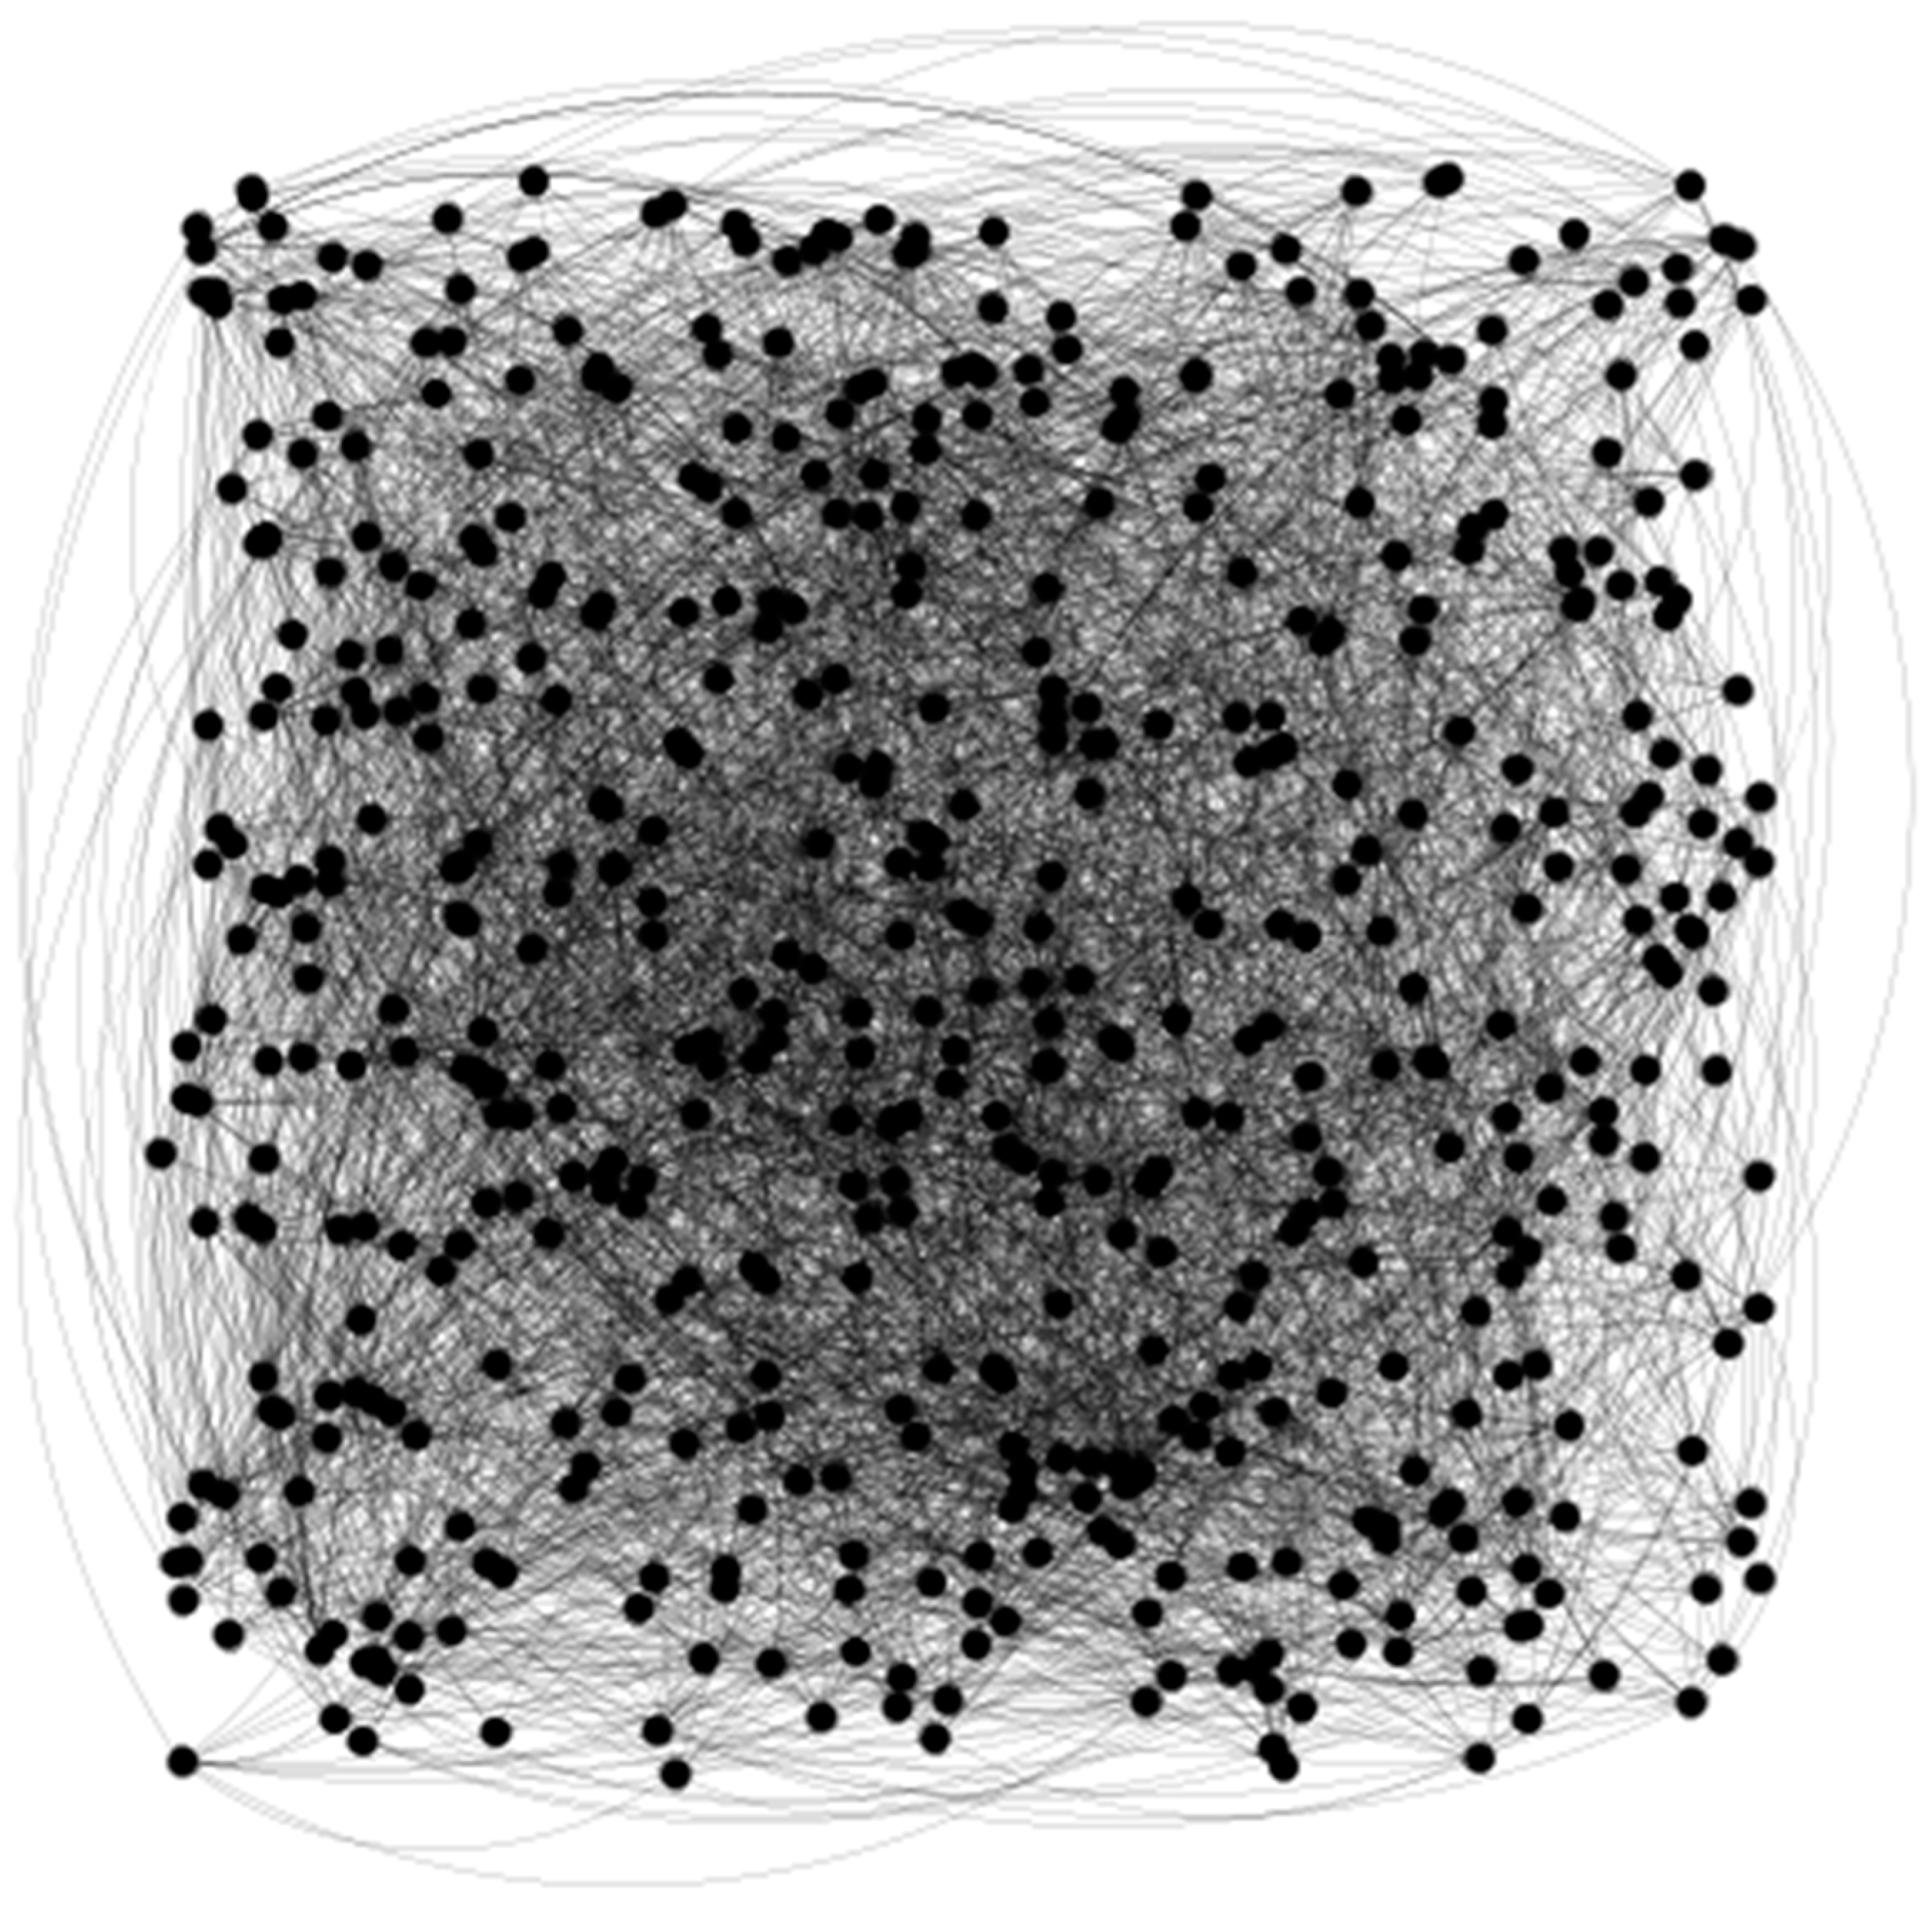

Traditional GNNs face challenges in effectively fusing features. They are also prone to over-smoothing, where node features converge excessively, reducing classification performance and limiting their utility in complex tasks. The advent of a Multi-order Neighbor Feature Fusion Graph Neural Network (MNFF-GNN) offers promising solutions to these limitations. The capability allows the MNFF-GNN to capture local relationships between node features better, mitigating the over-smoothing issue and enhancing the feature representation and fusion capabilities of traditional GNNs. Traditional methods for feature analysis often emphasize either local or global features but overlook the complex interaction relationships across different feature levels. This limitation hinders the extraction of deep-level information from data and impairs the ability to capture the essential characteristics of the disease comprehensively. As a result, feature mismatch arises, ultimately restricting the performance improvements achievable. The MNFF-GNN offers a promising solution that enables feature fusion. Specifically, the MNFF-GNN organizes and presents information from various neighbors in an interrelated manner, improving the compatibility and integration of features. Consequently, the MNFF-GNN enhances overall effectiveness and accuracy in artifact recognition applications. Graph attention networks (GATs) possess strong graph learning capabilities that can capture the real relationships in data and produce more accurate classification results with fewer training samples compared with general deep learning models. However, GATs only consider first-order neighborhoods, ignoring the influence of other nodes. In image analysis tasks, higher-order neighbors of nodes often contain important contextual information and long-range dependencies, which have potential value for artifact recognition as shown in Figure 1. To overcome this limitation, this chapter proposes an innovative Multi-order Neighbor Feature Fusion Graph Neural Network (MNFF-GNN) model.

After graph construction, we partly obtained a corresponding graph (see Figure 4).

The graph construction method as well as the topological characteristics and physical characteristics have been obtained as in [16].

Figure 1. Graph and neighborhood of the nodes.

Figure 4. Partial graph construction. The topological characteristics of the multi-order network, combined with physical characteristics, were fused as a node feature vector.